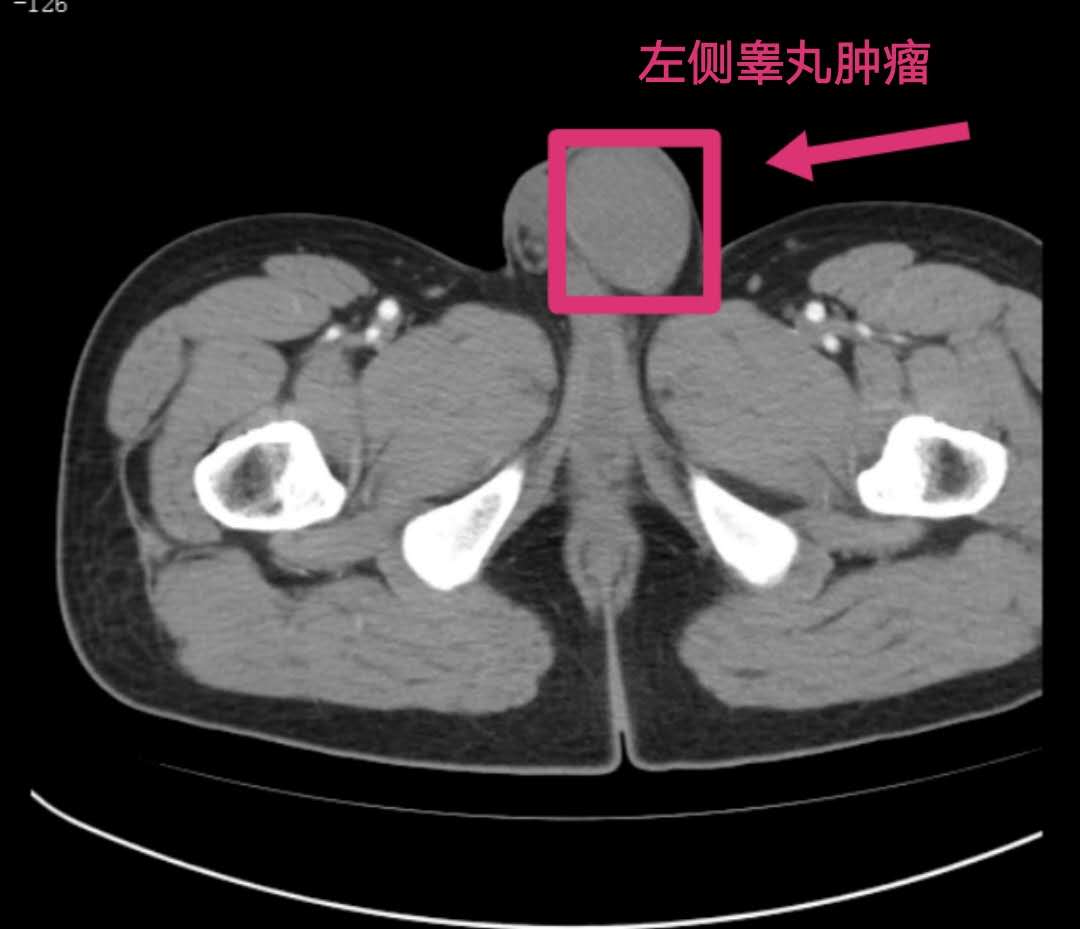

经检查发现,患者左侧睾丸增大,有肿瘤。在为其进行全麻下睾丸探查+睾丸根治性切除术后,病理结果确诊刘先生患的是睾丸精原细胞瘤,为睾丸恶性肿瘤。通过一周的精心护理,目前,刘先生已顺利出院。